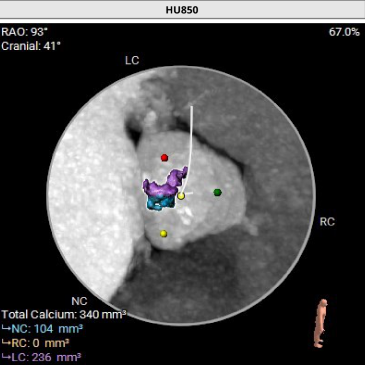

冠脉阻挡风险及钙化评估

• Type1型二叶式主动脉瓣,L-N间可见钙化融合嵴,瓣叶增厚伴中度钙化,综合预估瓣膜锚定难度尚适中,瓣膜植入后受钙化融合嵴挤压影响存在形变及移位的风险,瓣周漏、瓣中瓣风险适中;

• 左右冠瓣叶冗长,切线位左右冠瓣叶长度>>冠脉开口到瓣叶根部附着缘距离,结合瓦氏窦、STJ、钙化分布特点综合预估冠脉堵塞风险偏高,术中球扩时密切关注冠脉血流灌注,备冠脉保护方案;